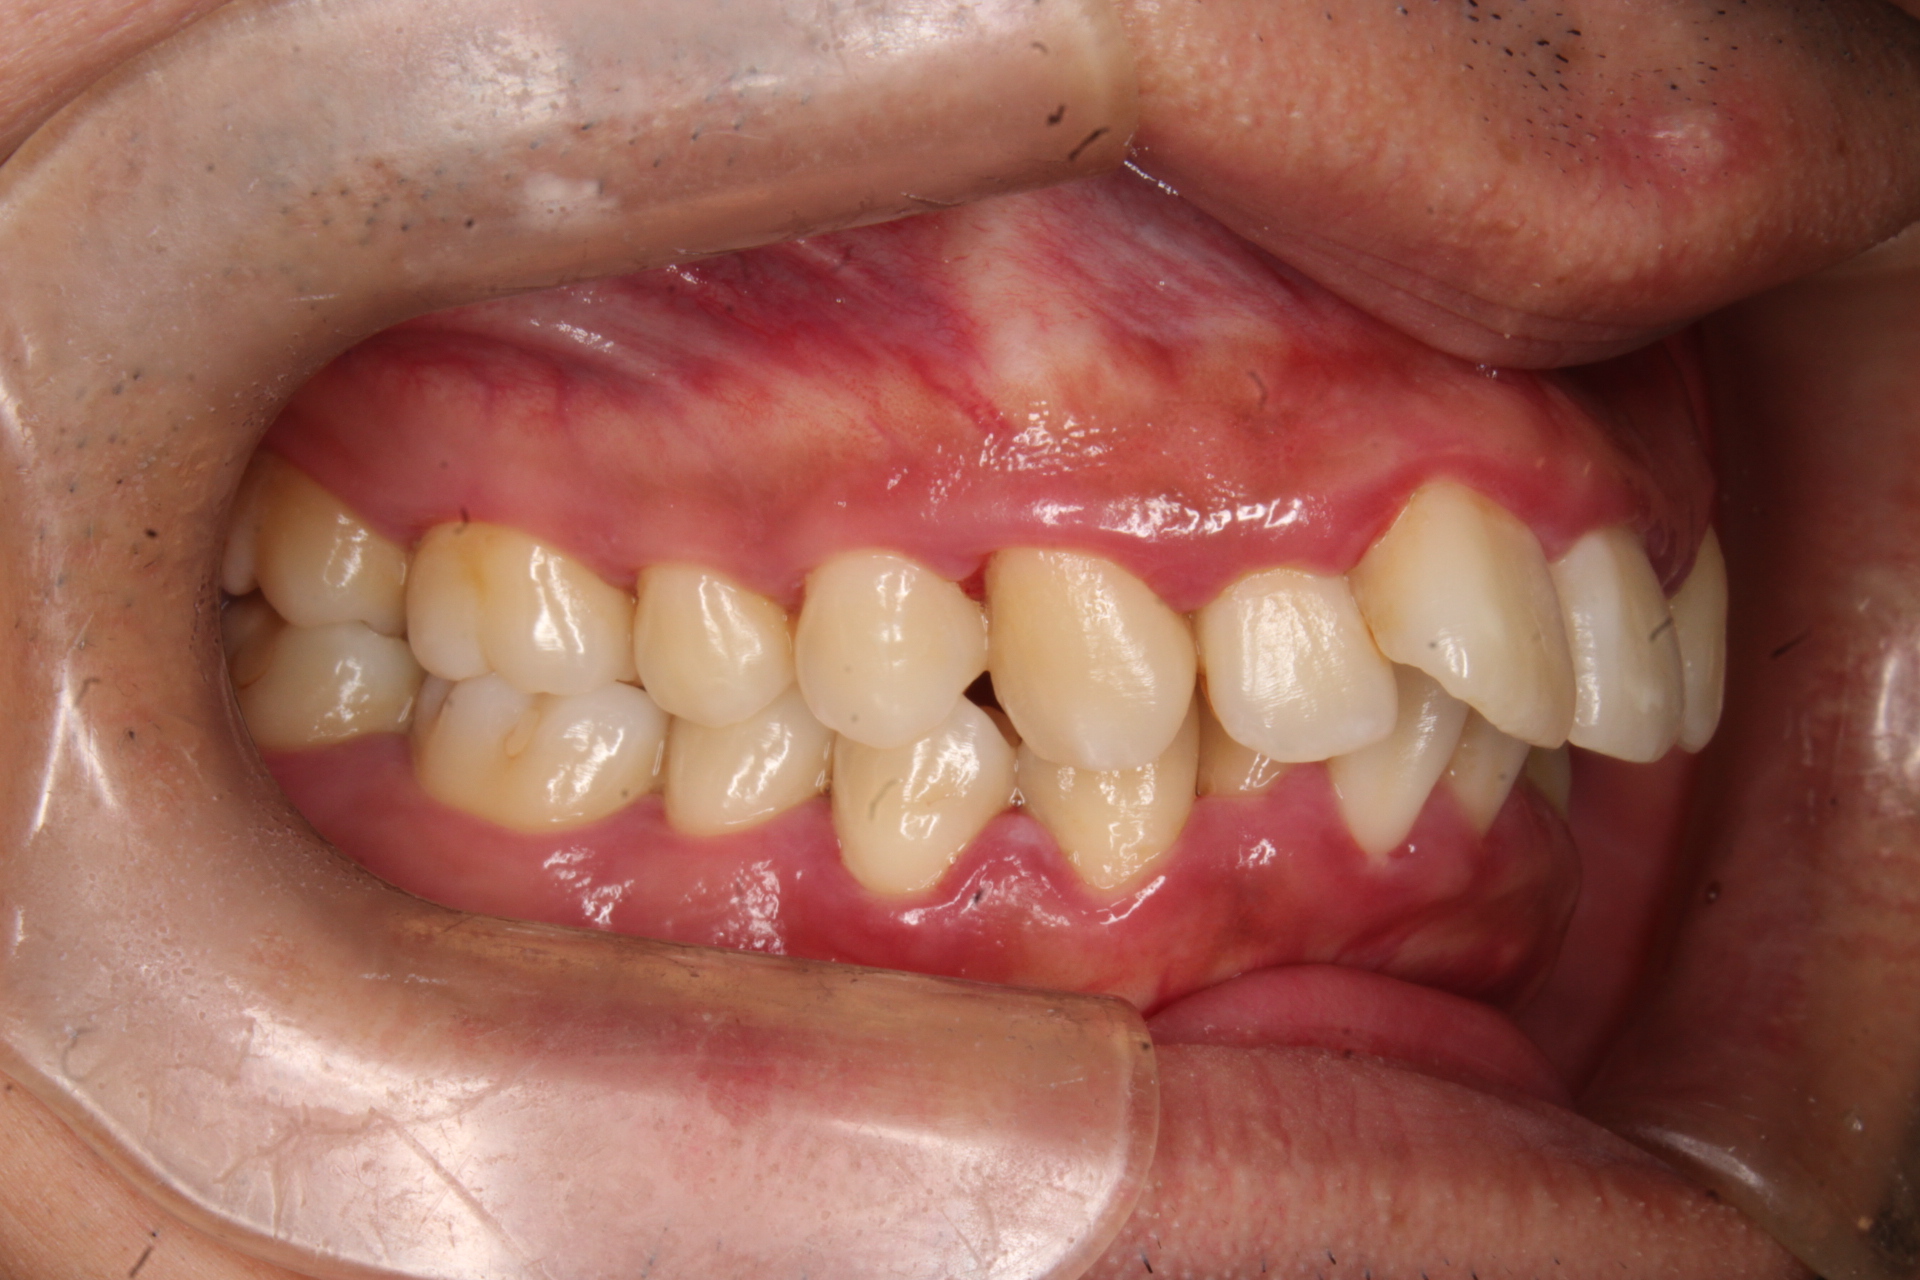

出っ歯を治したい

年齢層 30代

性別 女性

主訴 【主訴】出っ歯を治したい 【診断・症状】上下凸凹、出っ歯(上顎前突)

治療費用 検査・診断:38,500-/裏側矯正治療:1,397,000-(※全て税込)

治療期間 約2年半(33回)

抜歯 有(上4,4、下5,5)

矯正の装置 裏側矯正(舌側矯正)

副作用、リスク 歯肉退縮,歯根吸収,疼痛,咬合の違和感,装置の違和感,虫歯,歯肉炎

case20_出っ歯_before

Before

case20_出っ歯_after

After